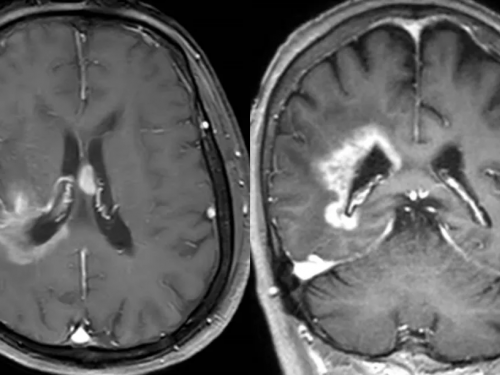

【山肿特色医疗技术】我院神经外科多方案联合成功救治室管膜、软脑膜广泛播散延髓脑干胶质瘤危重患者